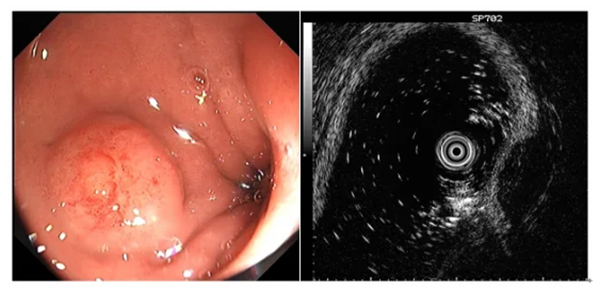

圖示超聲內(nei)鏡判斷(duan)黏膜下腫物(wù)性質(zhi)

微信(xin)截圖_20240417142333.jpg